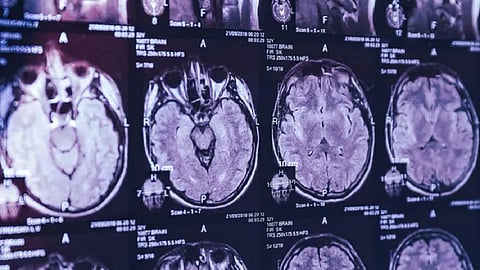

أعرب أطباء في إحدى الولايات الكندية عن تخوفهم من ظهور مرض غامض يصيب المخ غير معروف، مع إصابة عشرات من المواطنين بأعراض شديدة بينها فقدان الذاكرة وهلوسات وضمور بالعضلات.

وظهرت التفاصيل الأولى للتحقيق مع تسريب مذكرة، الأسبوع الماضي، من وكالة الصحة العامة بالولاية، تطالب الأطباء بالبحث عن أعراض شبيهة لمرض «كروتزفيلد جاكوب»، وهو مرض نادر قاتل يصيب المخ، تتسبب به بروتينات مشوهة تعرف بالبريونات.

وقالت المذكرة: «نتعاون مع مجموعات وطنية مختلفة وخبراء، ومع ذلك، لا يوجد سبب واضح للإصابة توصلنا اليه حتى الآن». وتشمل أعراض الإصابة بهذا المرض الغامض فقدان الذاكرة ومشاكل بالنظر وتشنجات غير طبيعية. ورغم تشابه الأعراض، لم ينتج الفحص عن أي حالات إصابة مؤكدة بمرض «كروتزفيلد جاكوب».